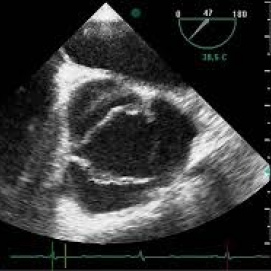

Ecocardiograma transesofagico. 881205 Idime (2022)

Bogotá, Bucaramanga |

$400000 |

BOGOTA:

Calle 77: Calle 77 No. 13 - 35

Sede Occidente: Av. de las Américas No. 69C - 94

Toberín: Carrera 19 B 168 - 53

BUCARAMANGA

Carrera 27 No. 30 - 15 Segundo Piso Hospital Universitario Los Comuneros